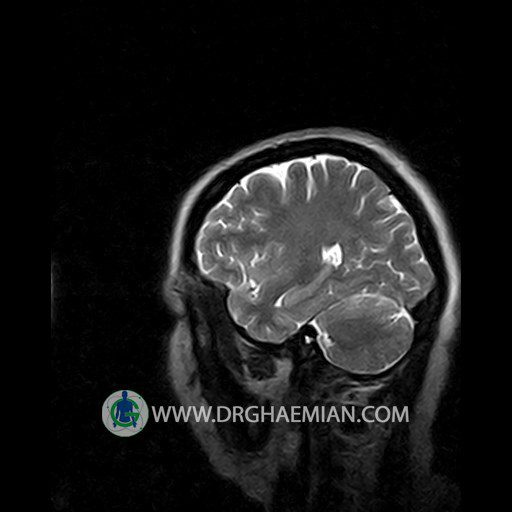

پزشکان اغلب از تصویربرداری ام آر آی برای تشخیص و درمان عارضه های پزشکی که فقط با استفاده از اشعه ایکس یا میدان مغناطیسی و امواج رادیویی قابل مشاهده است، استفاده می کنند. دستگاه ام آر آی تصاویر دقیق از ساختار های داخلی بدن ایجاد می کند. در این کیس نوریت اوربیت چب و سلای خالی بیمار مشاهده می شود.

Technique:Axial T1 , Axial , sagittal , coronal FSE T2 , coronal T1, sagittal fat sat T2 , Axial , sagittal T1 post Gd .

– Small fluid around the left optic nerve with mild edema suggestive for left optic neuritis

– Extension of suprasella cistern to sella with thin pituitary gland in floor of sella ( empty sella )

are seen